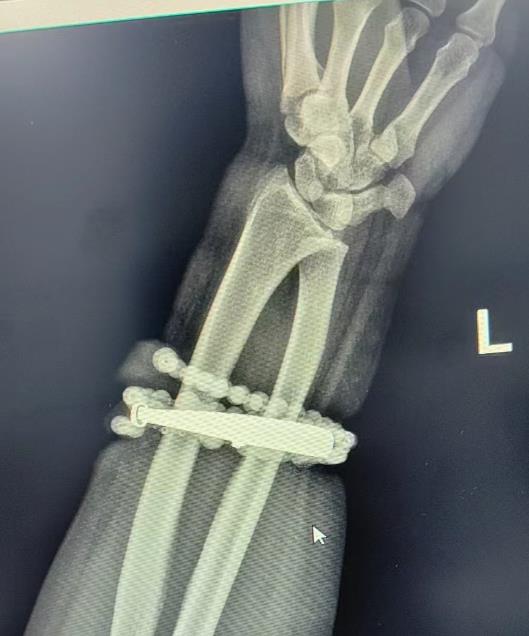

經(jīng)過(guò)一個(gè)多小時(shí)的手術(shù),醫(yī)生們將手鐲和串珠從厚厚的增生組織中完整剝離出來(lái)。目前,龔女士恢復(fù)良好,已順利出院。